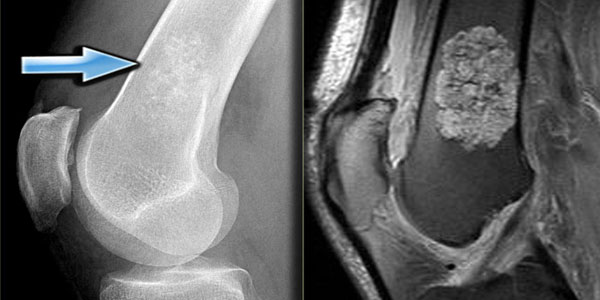

Osteokondrom - Ekzostoz

Osteokondroma en sık iyi huylu kemik tümörüdür (%35). Erkeklerde biraz daha sık. Bir çoğuna 20 yaşına kadar tanı konur.